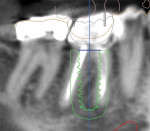

A 62-year-old healthy female presented with recurrent caries on tooth No. 30 (Figure 1). Tooth No. 30 was deemed non-restorable, and implant reconstruction was advised. A digital workflow was initiated for the flapless removal of tooth No. 30 and immediate implant placement.

A CBCT image (Figure 2) and digital impression (Figure 3) were obtained for diagnosis and treatment planning. To facilitate this, the CBCT image and impression were merged into the implant planning software for evaluation. Tooth No. 30 was removed from the virtual model, and a virtual restoration was created (Figure 4). Next, the vital structures and osseous anatomy were identified, and a virtual implant was planned (Figure 5 and Figure 6). A virtual fully guided surgical template was created (Figure 7) and then sent to the in-office printer for guide fabrication (Figure 8 and Figure 9). Using a flapless technique, the crown of tooth No. 30 was removed, and the necrotic roots were sectioned and surgically removed (Figure 10 and Figure 11). Following this, the CT template was placed, the osteotomies were completed, and the implant was placed in a guided fashion with 60 Ncm of torque (Figure 12 and Figure 13). After the osseous socket was grafted with allogenic bone, a healing abutment was placed, and the tissue was stabilized without mobilization using 3-0 chromic sutures (Figure 14 and Figure 15). An immediate post-operative CBCT scan was used to verify that the implant was placed as planned (Figure 16 and Figure 17).